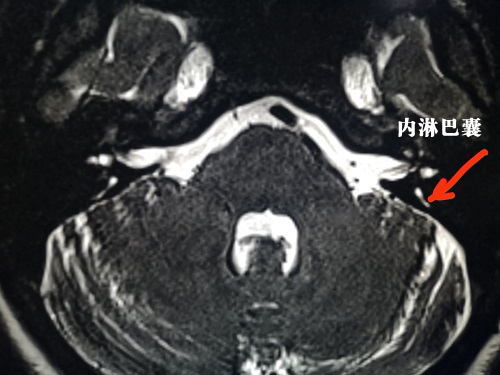

47歲女性患者,因反復(fù)頭暈伴耳鳴兩年入院,2年前開始出現(xiàn)頭暈,平均每月一次,近半年來發(fā)作頻繁,平均每月三到四次,聽力逐漸下降,在多家醫(yī)院就診,給予藥物治療無改善,嚴(yán)重影響生活,來我院就診,診斷梅尼埃病三期。

425日,我院耳鼻喉科胡少爭主任聯(lián)合河南省人民醫(yī)院劉軍教授為患者實(shí)施登封首例“乳突根治術(shù)+內(nèi)淋巴囊減壓術(shù)+半規(guī)管填塞術(shù)”該手術(shù)全程在顯微鏡下進(jìn)行,操作精細(xì)。術(shù)后患者無發(fā)熱、感染、面癱等手術(shù)并發(fā)癥出現(xiàn),恢復(fù)效果滿意。